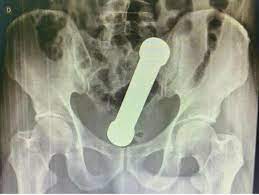

Ao realizarem um exame de raio-X, os médicos encontraram um peso de dois quilos, de cerca de 20 centímetros de comprimento, como os que são usados em academias de ginástica para exercícios de braço, dentro do homem.

O haltere estava entre o reto e o intestino grosso do paciente, que, depois do exame, admitiu ter introduzido o peso de academia no corpo para obter satisfação sexual.